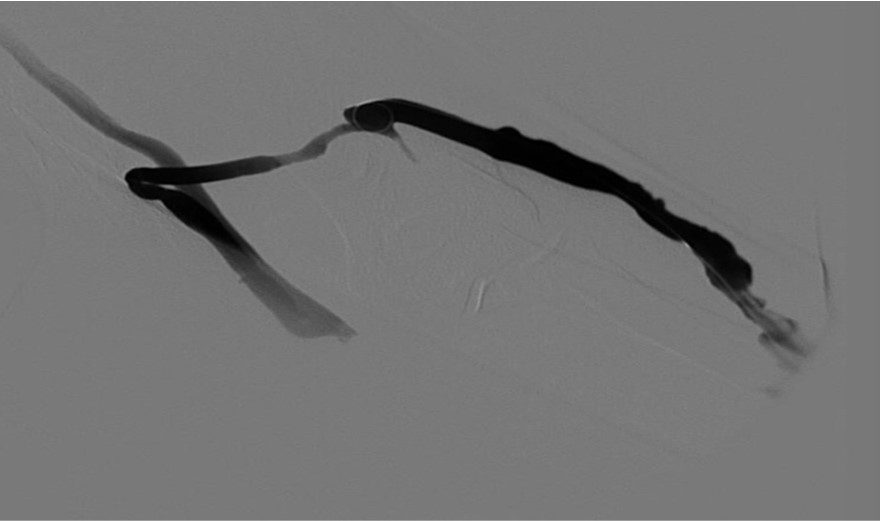

Fig. 6.

Criss-Cross “double-balloon” technique in left basilic van